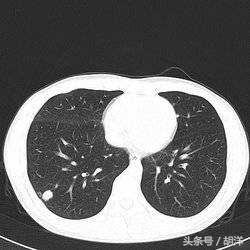

肺结核是一种常见的传染病,是由于结核菌感染造成的肺部结构破坏性疾病,其发生不单单有结核菌在肺部生长增殖并破坏肺部结构的因素,也有免疫细胞在与结核菌相互作用释放一些酶类造成肺部损害的因素,肺结核常常会出现钙化灶,特别是以往患有结核愈合后留下的疤痕,常常以钙化的形式存在,可以这么说钙化灶是肺结核愈合的表现,或者是陈旧性病灶的标志。

大部分情况下,病灶中只要有活的结核菌就不会出现钙化病灶,因为能够产生钙质的细胞不能在活动性结核病灶中存活,所以只要出现钙化,说明分泌钙质的细胞在病灶中站稳了脚跟并开始分泌钙质正常工作,病灶中要么结核菌已经被清除,要么出于休眠期。

钙化灶是肺部损伤病灶的修复机制,出现钙化大部分说明病灶中的病原体已经没有活性,在鉴别诊断中,钙化灶大多数时候是排除肿瘤的特征性标志。